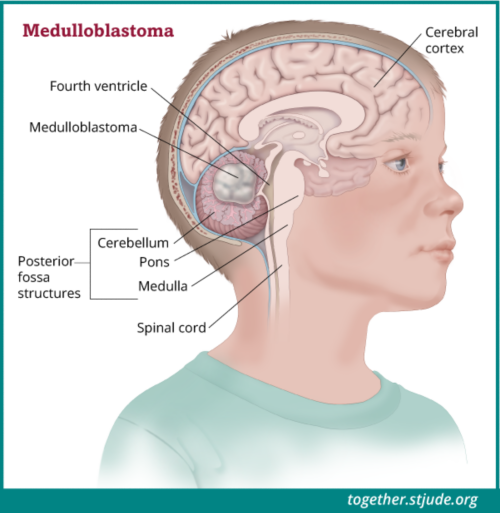

लग त र स र दर द ह सकत ह ब र न ट य मर क स क त ज न लक षण और इल ज brain tumor sign continue headache know brain tumor symptoms and treatment news nation (फाइल का प्रकार jpg)

लग त र स र दर द ह सकत ह ब र न ट य मर क स क त ज न लक षण और इल ज Brain Tumor Sign Continue Headache Know Brain Tumor Symptoms And Treatment News Nation